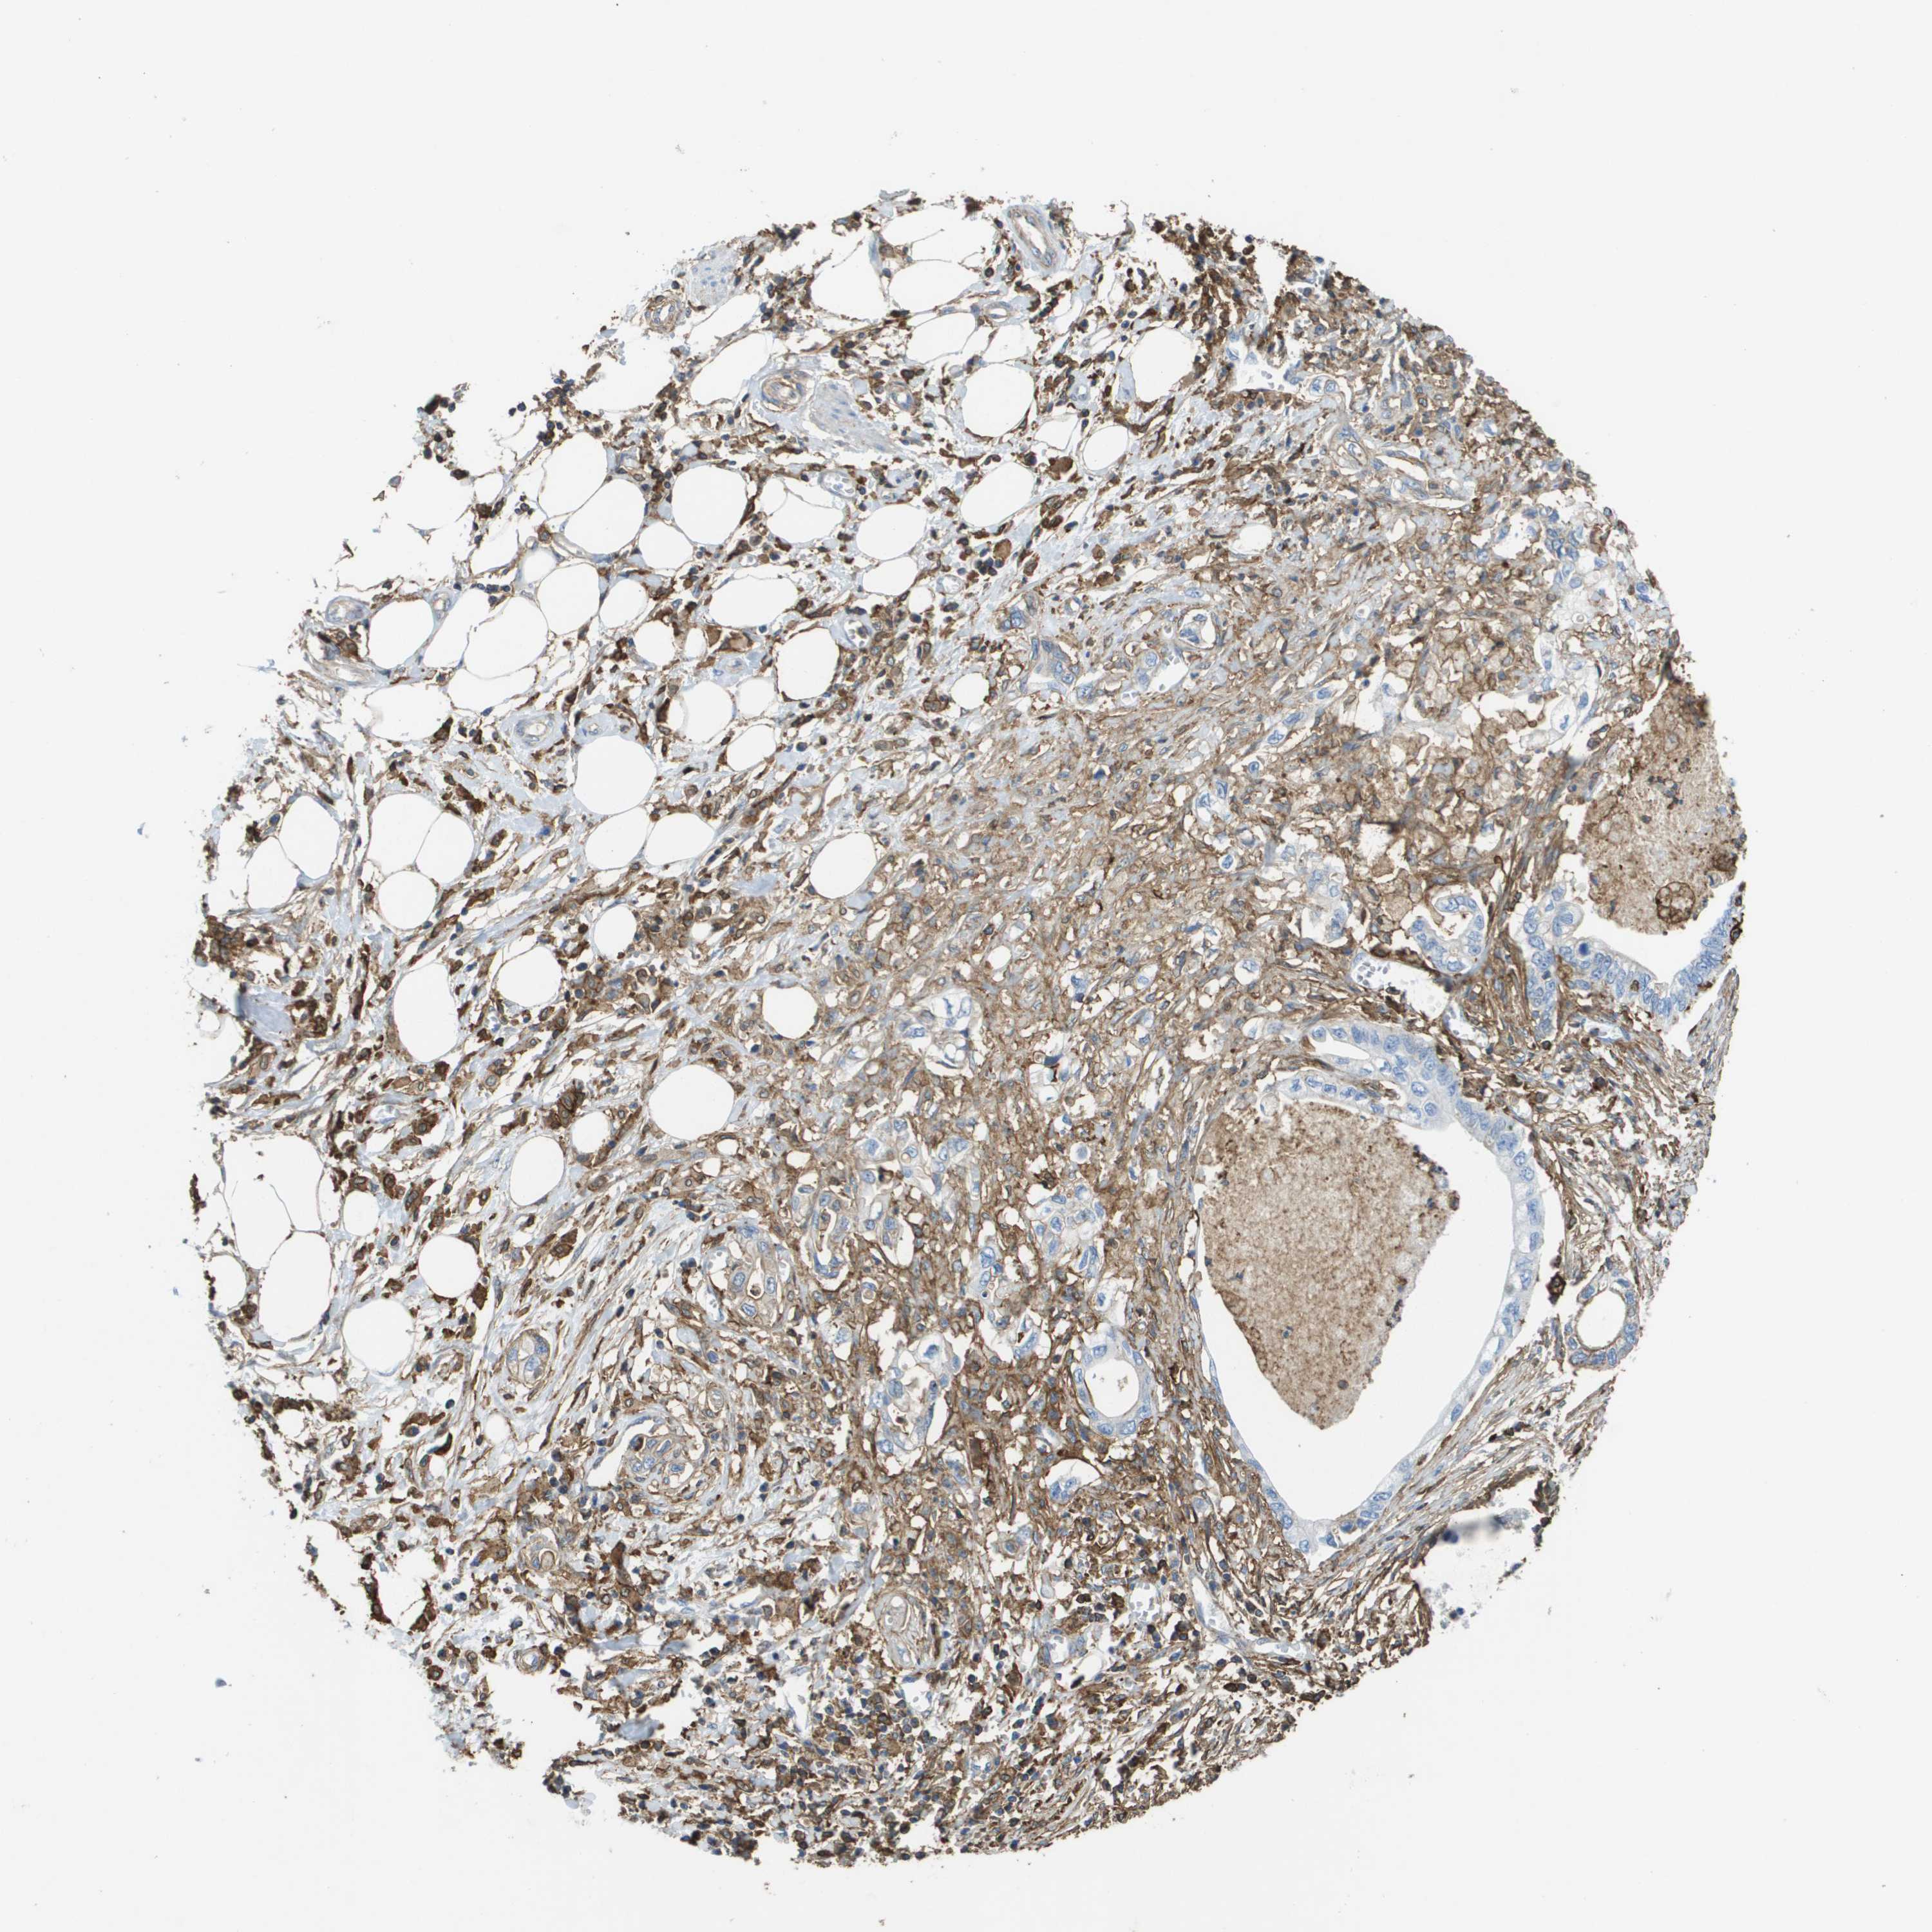

PANCREATIC CANCER - Protein expressioni

A mouse-over function shows sample information and annotation data. Click on an image to view it in a full screen mode. Samples can be filtered based on level of antibody staining by selecting one or several of the following categories: high, medium, low and not detected. The assay and annotation is described here.

Note that samples used for immunohistochemistry by the Human Protein Atlas do not correspond to samples in the TCGA dataset.

Antibody stainingi

Antibody staining in the annotated cell types in the current human tissue is reported as not detected, low, medium, or high, based on conventional immunohistochemistry profiling in selected tissues. This score is based on the combination of the staining intensity and fraction of stained cells.

Each image is clickable and will lead to virtual microscopy that enables deeper exploration of all samples and also displays staining intensity scores, fraction scores and subcellular localization as well as patient and tissue information for each sample.

Antibody HPA016450

Antibody HPA021079

Staining

High

Medium

Low

Not detected

Intensity

Strong

Moderate

Weak

Negative

Quantity

>75%

75%-25%

<25%

None

Location

Nuclear

Cytoplasmic/membranous

Cytoplasmic/membranous,nuclear

Adenocarcinoma, NOS